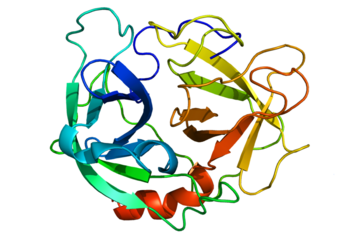

Annexin A3 as a Diagnostic Biomarker and Therapeutic Target for Treating Hepatocellular Carcinoma

Proteins for Serological Test of COVID-19

PD1-Based TWIST1 Cancer Vaccine

Aptamers for the Treatment of Osteoporosis